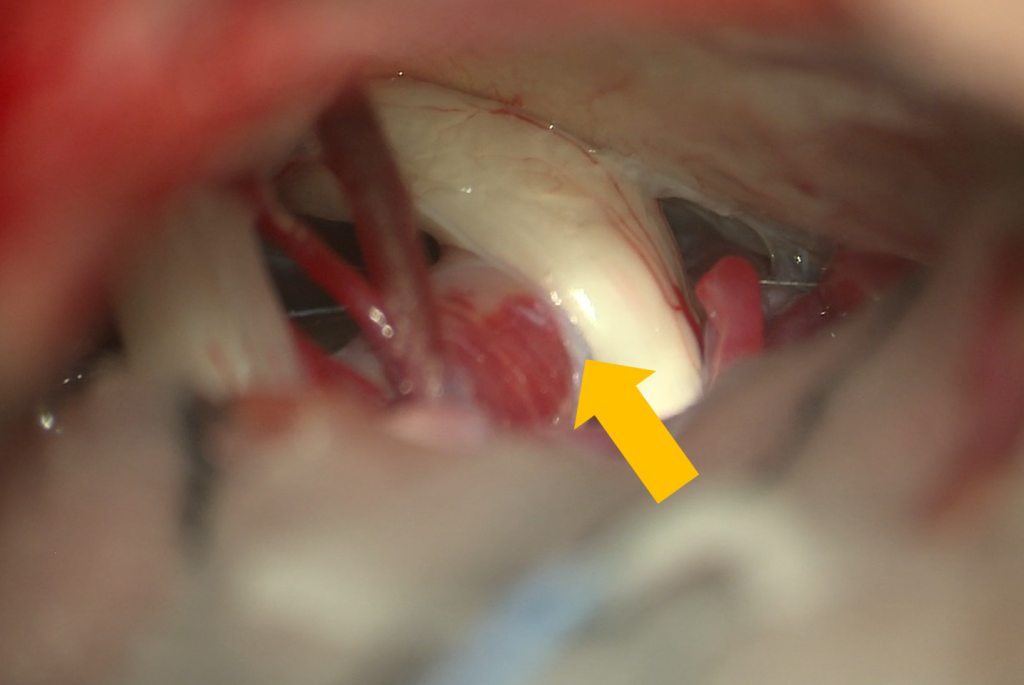

脳動脈瘤クリッピング術

巨大脳動脈瘤に対するハイフローバイパス(黄矢印)術後。動脈瘤は消失し、 脳の血流は正常に保たれている。

大型脳動脈瘤に対するsuction decompressionによるクリッピング